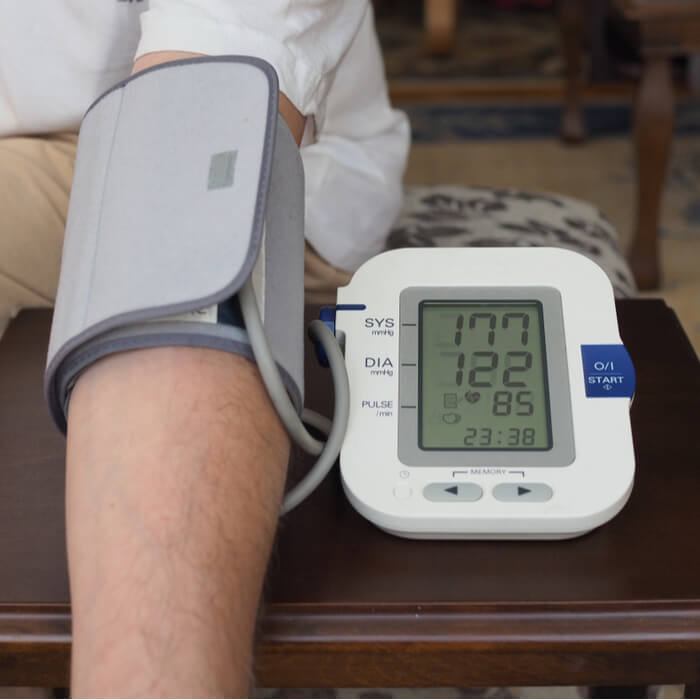

7 Votre pression artérielle est élevée : le magnésium aide à dilater et à détendre vos vaisseaux sanguins. Logiquement, une carence en magnésium peut provoquer une hypertension artérielle en augmentant la constriction des vaisseaux sanguins.